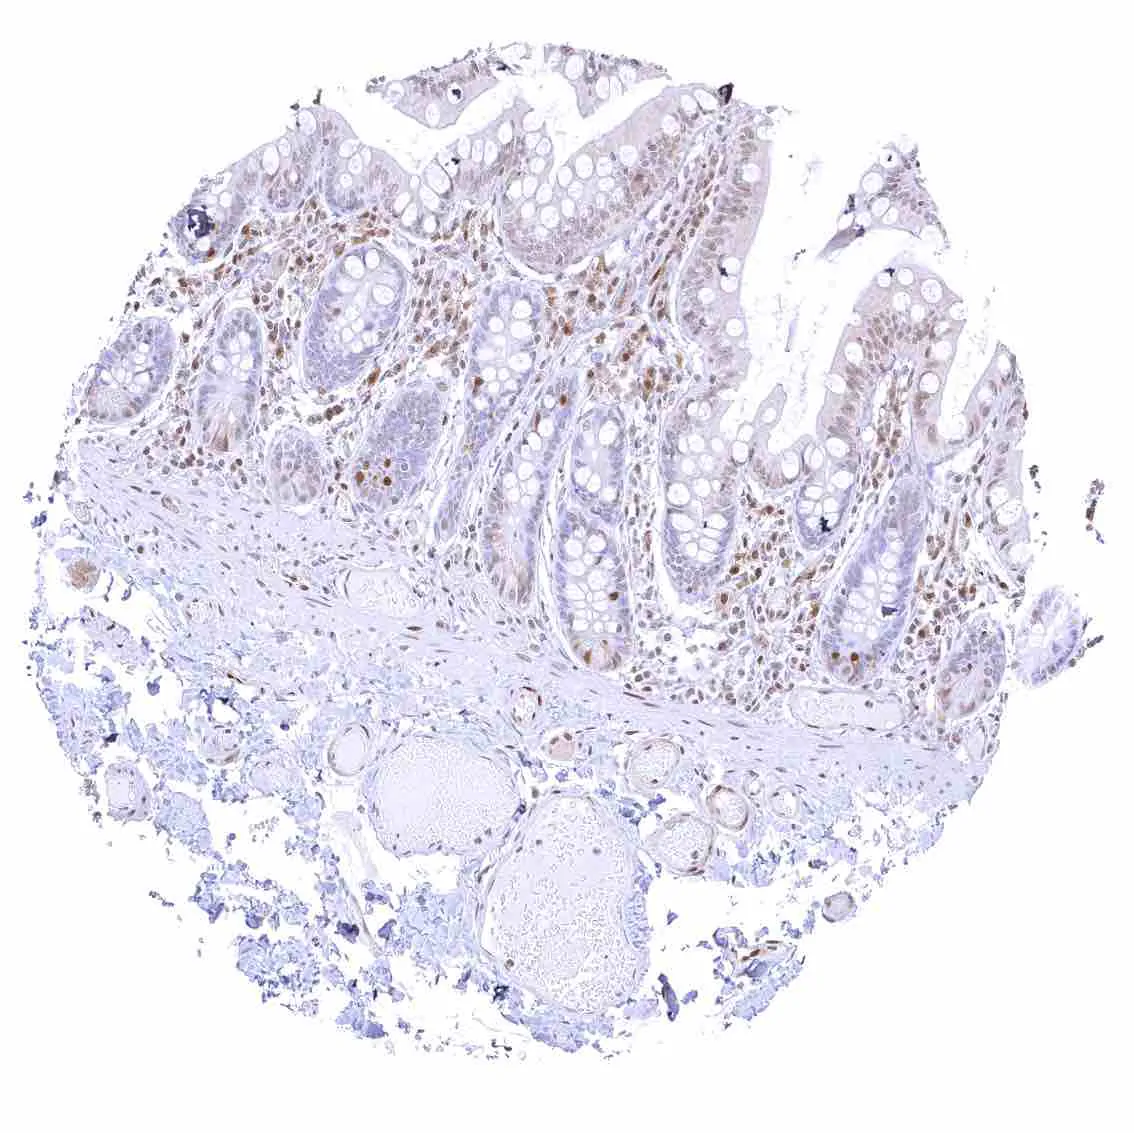

Appendix, mucosa – Among epithelial cells, nuclear p27 staining predominates in superficial epithelial cells. Most p27 staining occurs in lymphatic cells, however.